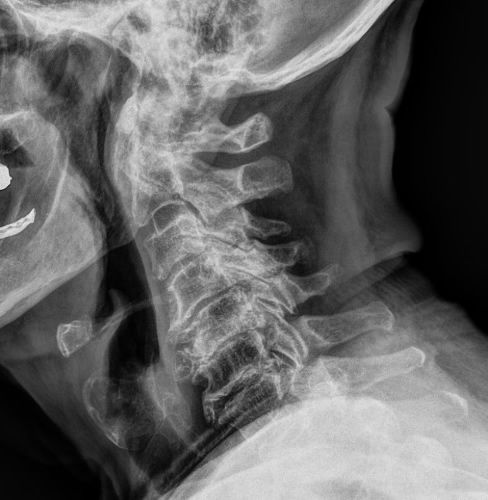

Οι ακτινογραφίες πραγματοποιούνται με πλήρως ψηφιακό εξοπλισμό και όχι ψηφιοποιημενο από έμπειρους Τεχνολόγους – Ακτινολόγους με άδεια ασκήσεως Επαγγέλματος.

Ο πιο σύγχρονος φορητός Ακτινολογικός εξοπλισμός πλήρως ψηφιακής απεικόνισης (DR) σε μια κινητή ακτινολογική μονάδα, μπορεί να επισκεφθεί τον ασθενή οπουδήποτε στην περιοχή της Θεσσαλονίκης και των περιχώρων και να σταλεί, αν ο ασθενής το επιθυμεί, η γνωματευμένη ακτινογραφία ηλεκτρονικά μέσω διαδικτύου στον θεράποντα- παραπέμποντα ιατρό ο οποίος θα λάβει το αποτέλεσμα στο προσωπικό του υπολογιστή, tablet, Smartphone οπουδήποτε κι αν βρίσκεται.